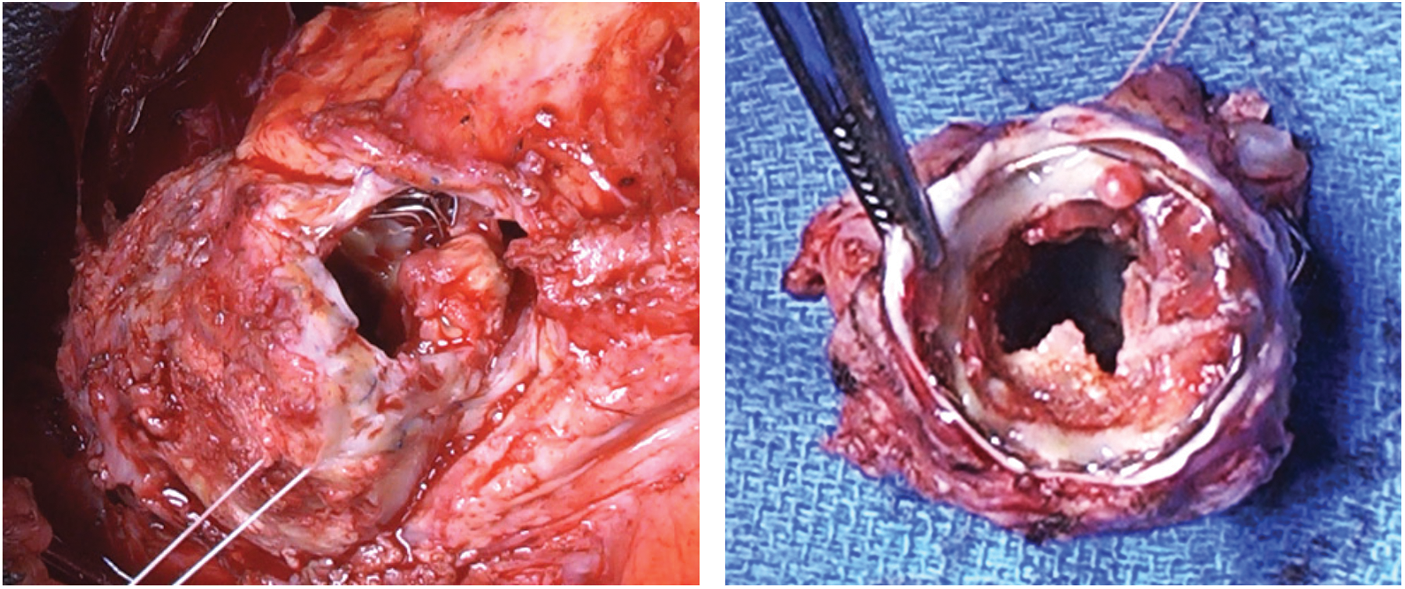

At surgery, after an uneventful repeat sternotomy, the diagnosis of mediastinitis was confirmed, with purulent material at the level of the old Gore-tex membrane used 18 years earlier to close the pericardium. This infection was adjacent to the anterior part of the Contrega Conduit (Fig. 2).

Figure 2: The infection on the Gore-tex membrane

Following the debridement, peripheral cardiopulmonary bypass (CPB) was initiated via the femoral vein and artery. On a beating heart, the right ventricle infundibulum was opened, the previously placed Contrega conduit was resected “en-bloc” together with the 3 stents and the Melody valve (Fig. 3). The prosthesis appeared calcified with large vegetations. A 26-mm pulmonary homograft (European Homograft Bank, St-Jean Clinic, Brussels) was used for RVOT reconstruction.

Figure 3: The large vegetation of the valve